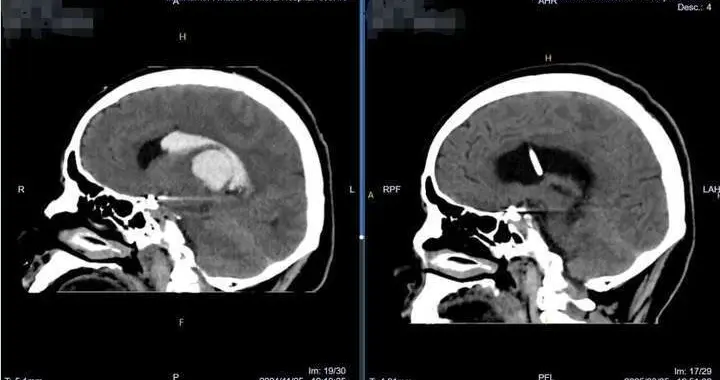

肖庆教授“脑内捉虫”:一根软镜,解决十年头痛